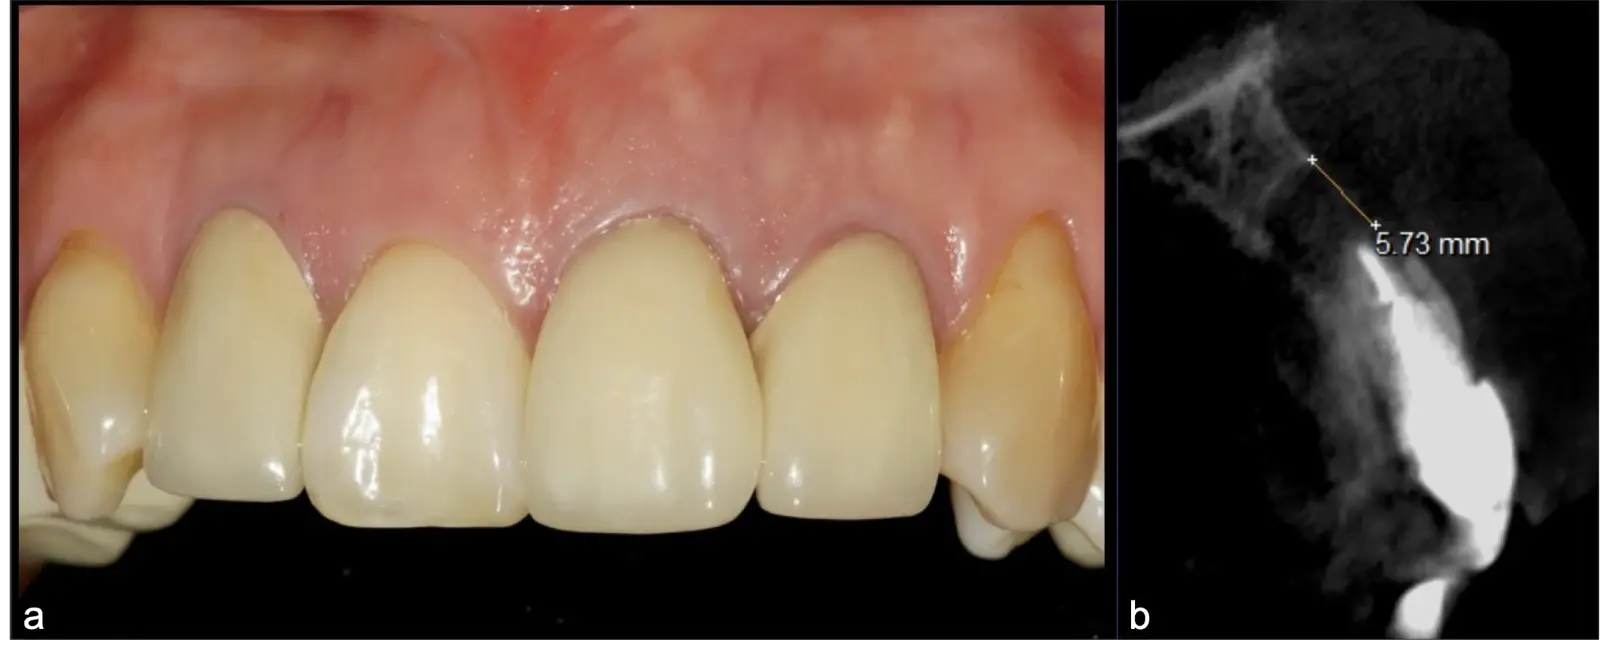

La microcirugía endodóntica apical busca conservar la mayor cantidad de longitud de raíz y de hueso circundante sano para no afectar la estabilidad de la pieza.11 Por ello, es ideal el uso de microscopios, elementos de magnificación, instrumental específico (insertos de ultrasonido endodónticos) y materiales de sellado eficientes para el tratamiento retrogrado. Su éxito es alto y evidencia una cicatrización ósea completa en el 74% de los casos al año de tratamiento.12 Cabe destacar que este logro está asociado también, a predictores propios de cada paciente, como la edad, tipo de pieza, profundidad de sondaje y extensión de la lesión.1 El uso complementario de la tomografía computarizada es resaltante como el instrumento imagenológico de elección para la etapa de planificación microquirúrgica,13 ya sea para una ejecución a mano alzada o con guías prefabricadas.14,15

El origen puede ser bacteriano (colonias bacterianas persistentes4, patología periodontal asociada5, reinfecciones por falta de sellado coronal), mecánico (preparación deficiente, fractura de instrumentos, fracturas radiculares6, extravasación de material de obturación7 con ó sin compromiso de estructuras vecinas) y anatómico (conductos accesorios poco permeables o calcificados)8 (Figuras 1 - 4).